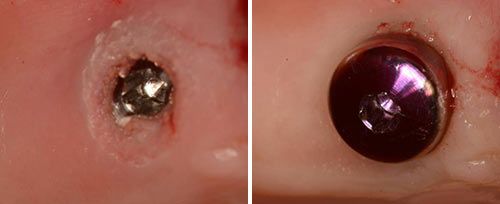

Implant Release

Courtesy of: Assist. Prof. Dragana Gabric, DMD, PhD

Laser source: Er:YAG (2940 nm)